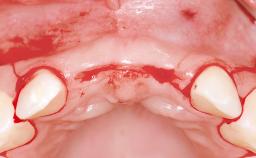

This 20-year-old woman was referred to our department in July 2006. Four months earlier, she had experienced dental trauma to the anterior maxilla when traveling in South America. The emergency treatment included emergency root canal treatment of teeth 12 and 11. Tooth 21 was also subjected to endodontic treatment later. At the initial examination, the patient was not in pain but reported increased mobility of tooth 12. The clinical examination revealed a high smile line, medium thickness of the soft tissue, and rectangular tooth forms. Discoloration of tooth 12 was evident. The periapical radiograph provided by the referring dentist indicated a fracture line at both teeth 12 and 11. A cone-beam computed tomography (CBCT) scan confirmed these fractures. No pathology was found to be associated with tooth 21.

| Bone Augmentation | Horizontal|Simultaneous |

| Augmentation Materials | Autogenous chips|Xenogenous|Membrane |

| Bone Volume | Deficient horizontally, allowing simultaneous augumentation |